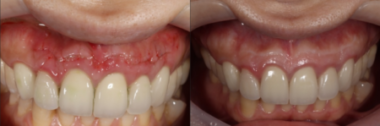

術後およそ2週間で、患者様が訴えていた違和感は大きく改善されました。

その後も3ヶ月、1年と経過を追って確認した結果、現在に至るまで外科手術による瘢痕はほとんど見られず

美しい歯のラインを維持したまま、無事に治療を完了することができました。

画像がこちらになります。

治療後画像①|【症例】セラミック治療後に発症した根尖性歯周炎に対する歯根端切除術|目白マリア歯科

左:術後3日 右:術後3ヶ月

治療後画像②|【症例】セラミック治療後に発症した根尖性歯周炎に対する歯根端切除術|目白マリア歯科

術後1年